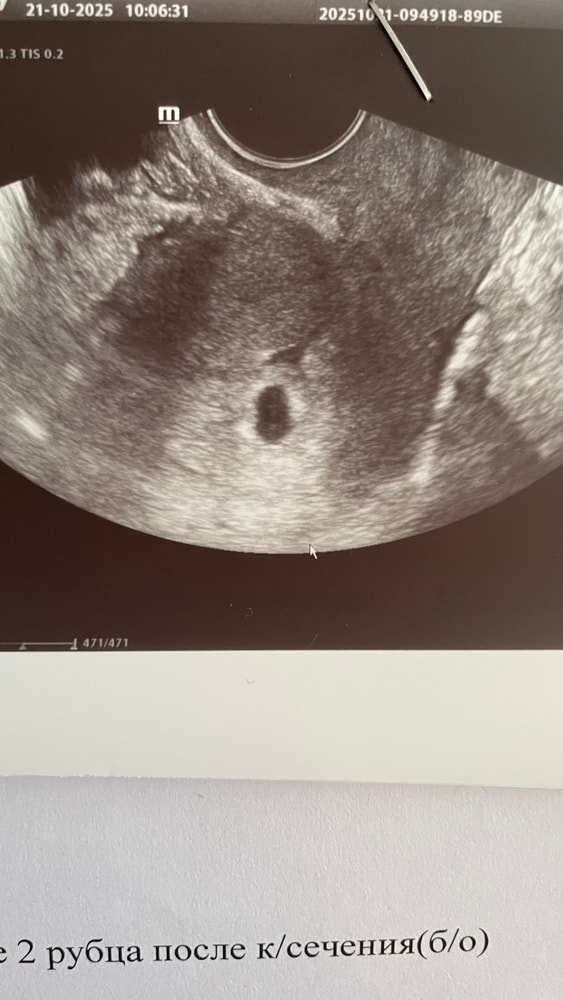

УЗИСходила на узи наше первое) срок по м 4.6, овуляция была раньше, потому так рано и пошла, что б убедиться, что б маточная)

прикрепление по задней стенке, пя 8мм. Пока больше ничего не увидела, ну я и не расчитывала на большее.

Хотя если присмотреться, то что то там в пя виднеется, но я не спец в этом конечно, доверюсь врачу)) Сказала на контроль через 10 дней вернуться, а сейчас расслабиться. Больше от нас никак сей процесс не зависит